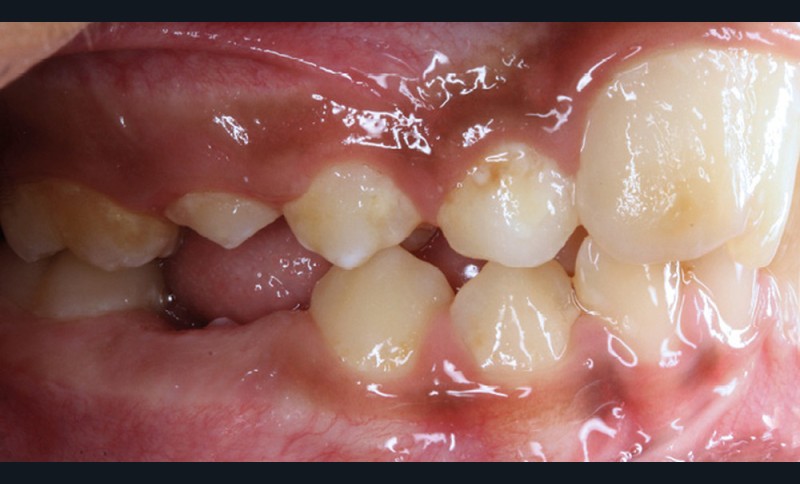

Antony, 11 ans se présente initialement pour une demande esthétique concernant ses deux incisives centrales qu’il trouve trop grosses (fig. 1a-c).

Le profil est convexe et associé à une inocclusion labiale au repos. Il s’agit d’une classe II squelettique sur un schéma facial normodivergent. Les rapports occlusaux sont de classe II bilatérale (complète au niveau molaire) avec des incisives inférieures vestibulo-versées. La 21 est géminée et la 11 vraisemblablement fusionnée avec un germe surnuméraire, sans altération de la formule dentaire. Du fait du diamètre mésiodistal fortement augmenté des incisives centrales, et du manque de place à l’arcade maxillaire qui en découle, les 12 et 22 sont en inversé d’occlusion en palato position. Les 53 et 63 sont persistantes sur l’arcade avec une inclusion en transposition incomplète de la 13, dont la cuspide se situe entre la racine de la 12 et celle de la 11 résorbée (fig. 1d-g).